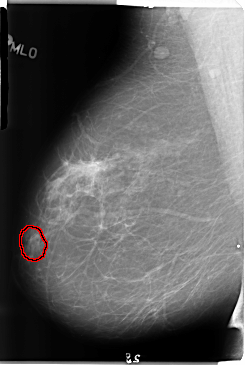

ics_version 1.0 filename B-3144-1 DATE_OF_STUDY 25 7 1997 PATIENT_AGE 43 FILM FILM_TYPE REGULAR DENSITY 2 DATE_DIGITIZED 5 5 1998 DIGITIZER LUMISYS LASER SEQUENCE LEFT_CC LINES 4832 PIXELS_PER_LINE 3080 BITS_PER_PIXEL 12 RESOLUTION 50 NON_OVERLAY LEFT_MLO LINES 4744 PIXELS_PER_LINE 3112 BITS_PER_PIXEL 12 RESOLUTION 50 NON_OVERLAY RIGHT_CC LINES 4704 PIXELS_PER_LINE 2904 BITS_PER_PIXEL 12 RESOLUTION 50 OVERLAY RIGHT_MLO LINES 4744 PIXELS_PER_LINE 3176 BITS_PER_PIXEL 12 RESOLUTION 50 OVERLAY |

FILE: B_3144_1.RIGHT_MLO.OVERLAY TOTAL_ABNORMALITIES 1 ABNORMALITY 1 LESION_TYPE MASS SHAPE IRREGULAR MARGINS ILL_DEFINED ASSESSMENT 4 SUBTLETY 2 PATHOLOGY BENIGN TOTAL_OUTLINES 1 BOUNDARY |